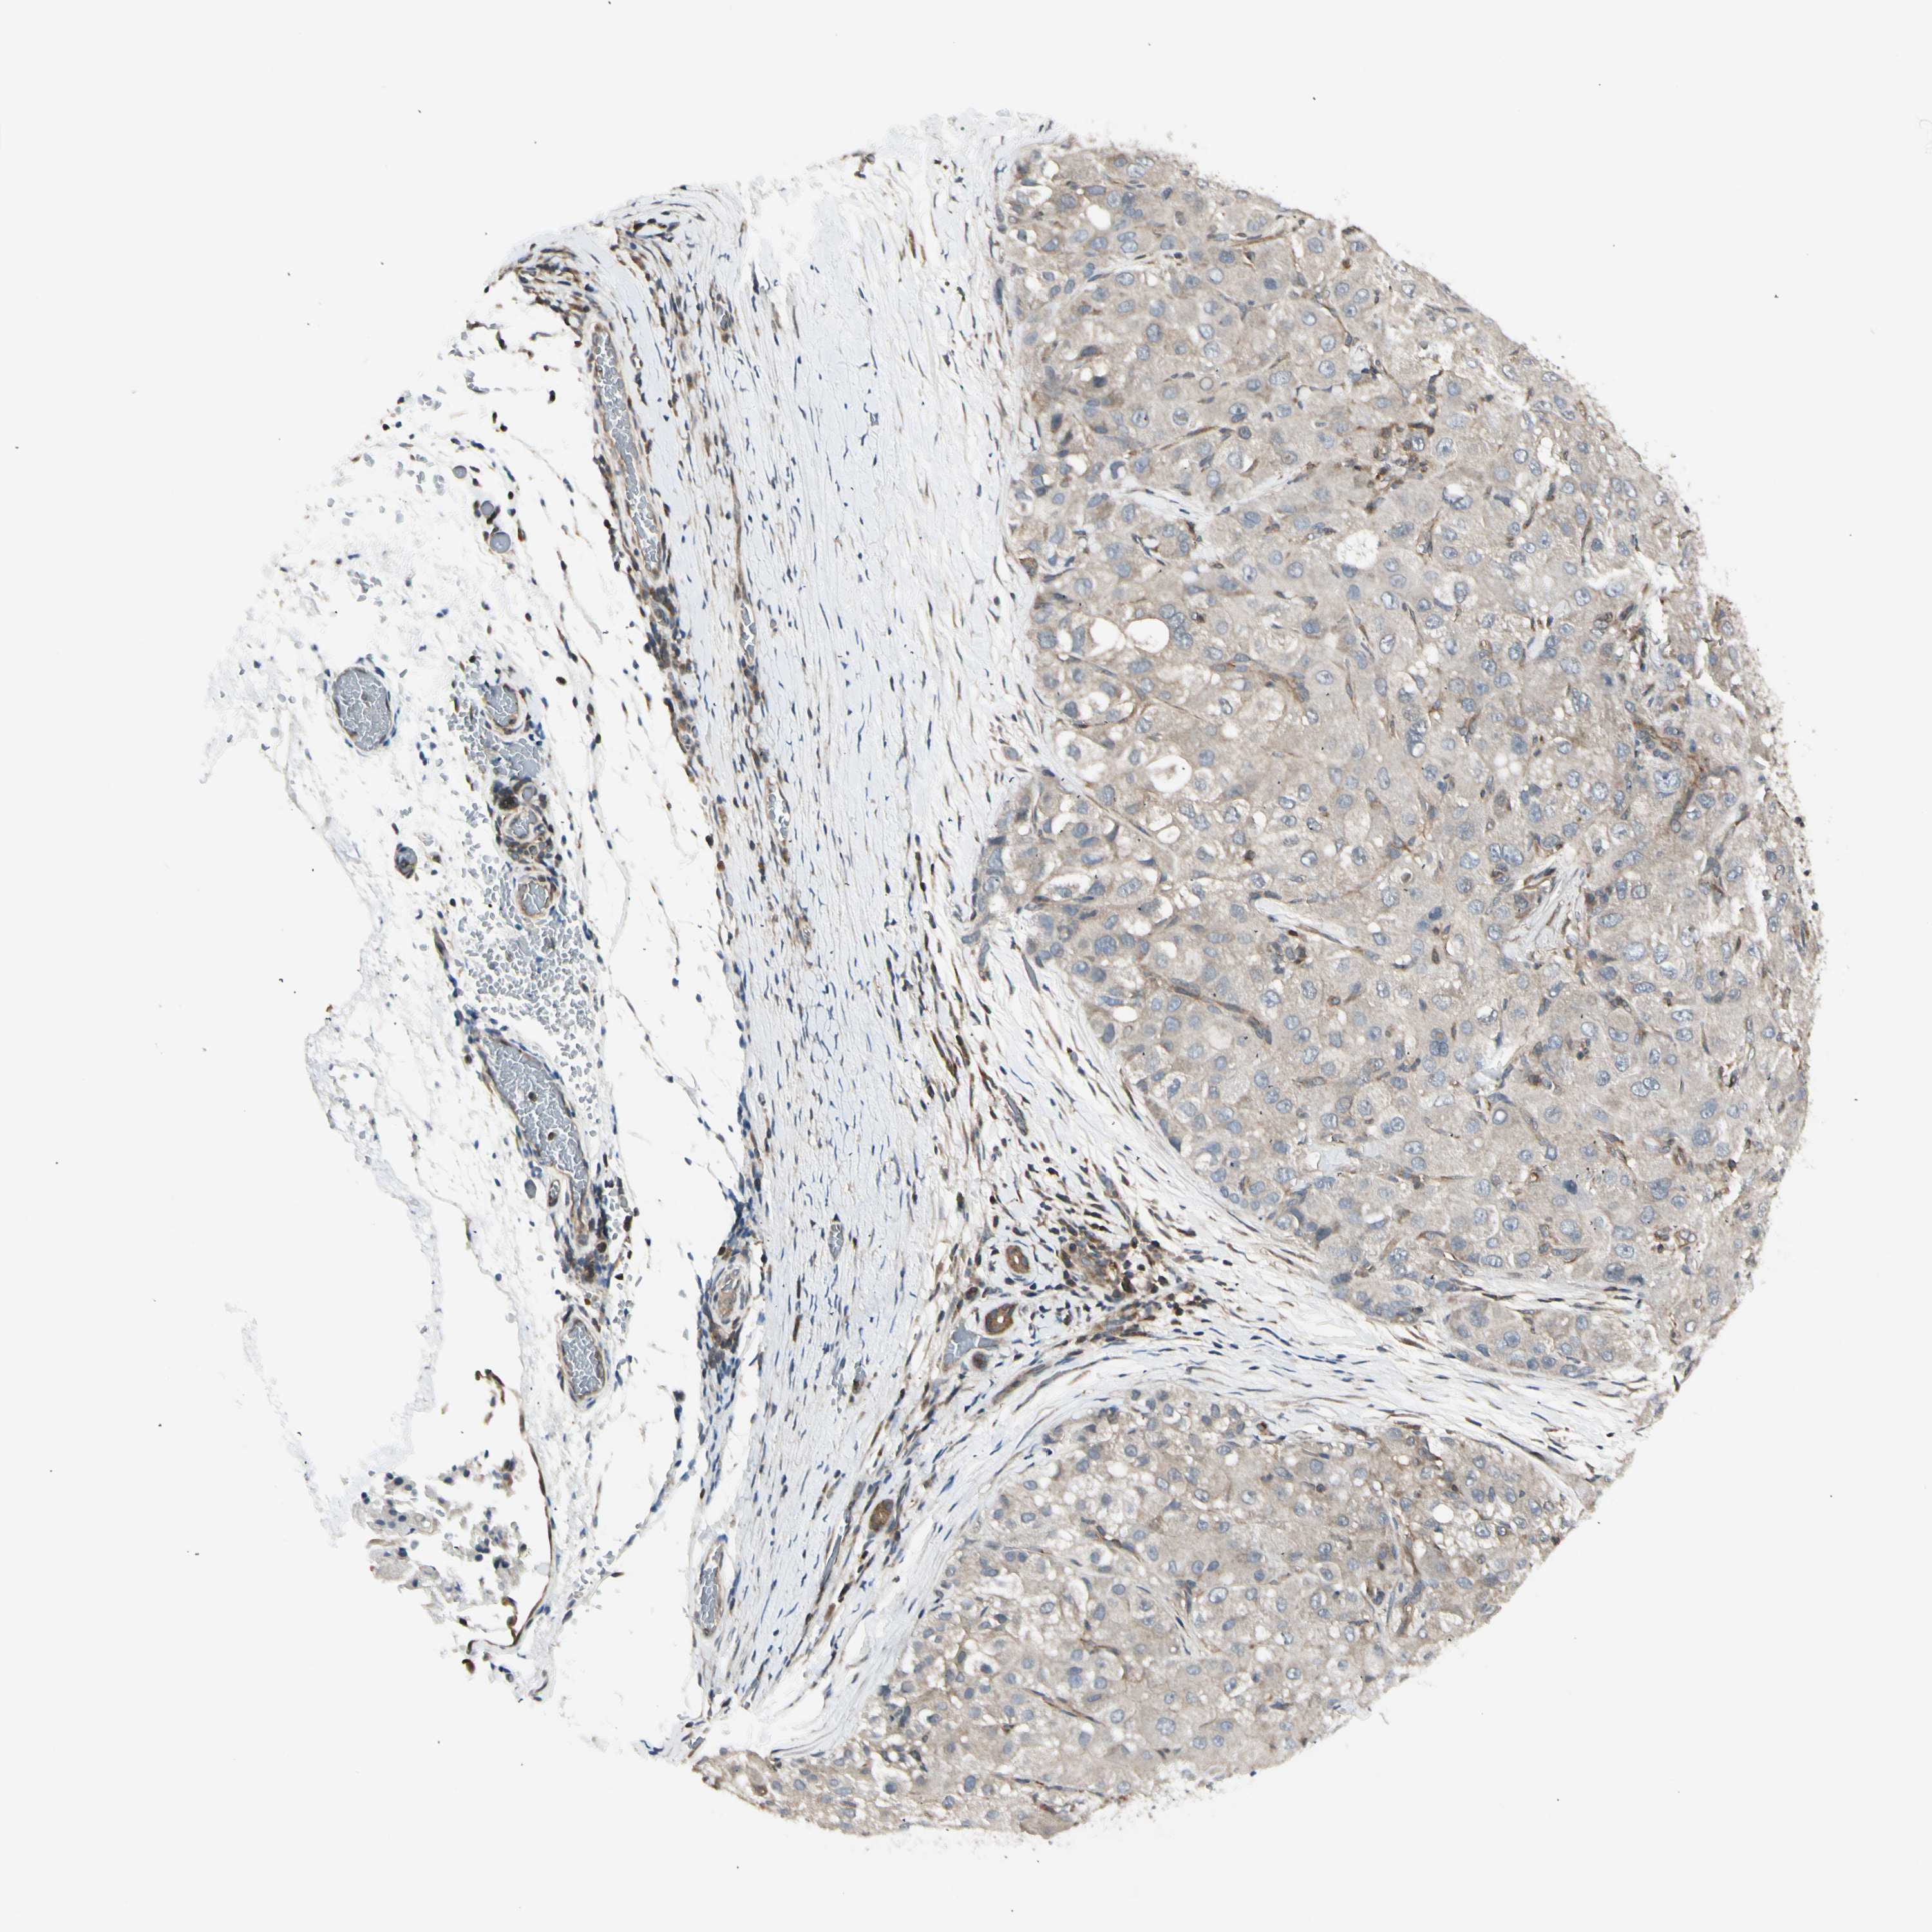

LIVER CANCER - Protein expressioni

A mouse-over function shows sample information and annotation data. Click on an image to view it in a full screen mode. Samples can be filtered based on level of antibody staining by selecting one or several of the following categories: high, medium, low and not detected. The assay and annotation is described here.

Note that samples used for immunohistochemistry by the Human Protein Atlas do not correspond to samples in the TCGA dataset.

Antibody stainingi

Antibody staining in the annotated cell types in the current human tissue is reported as not detected, low, medium, or high, based on conventional immunohistochemistry profiling in selected tissues. This score is based on the combination of the staining intensity and fraction of stained cells.

Each image is clickable and will lead to virtual microscopy that enables deeper exploration of all samples and also displays staining intensity scores, fraction scores and subcellular localization as well as patient and tissue information for each sample.

Antibody HPA008237

Antibody CAB017181

Staining

High

Medium

Low

Not detected

Intensity

Strong

Moderate

Weak

Negative

Quantity

>75%

75%-25%

<25%

None

Location

Nuclear

Cytoplasmic/membranous

Cytoplasmic/membranous,nuclear

Cholangiocarcinoma

Carcinoma, Hepatocellular, NOS